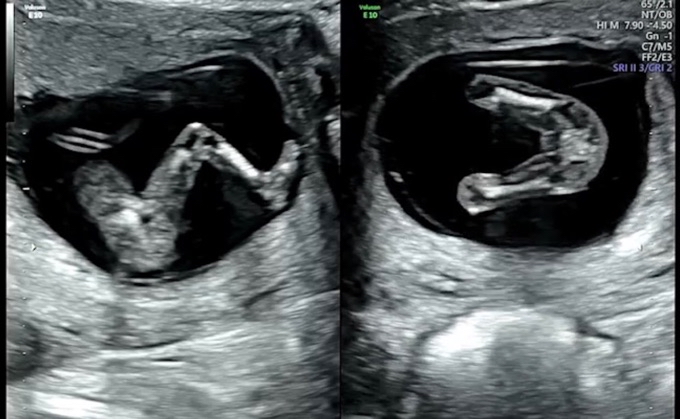

12주 초음파인데요 딸일까요 아들일까요?

아직 12주라 확실하진 않다고 하는데요

내심 딸을 바래서 이리보고 저리 보고 있어요

고수님들 알려주세요~